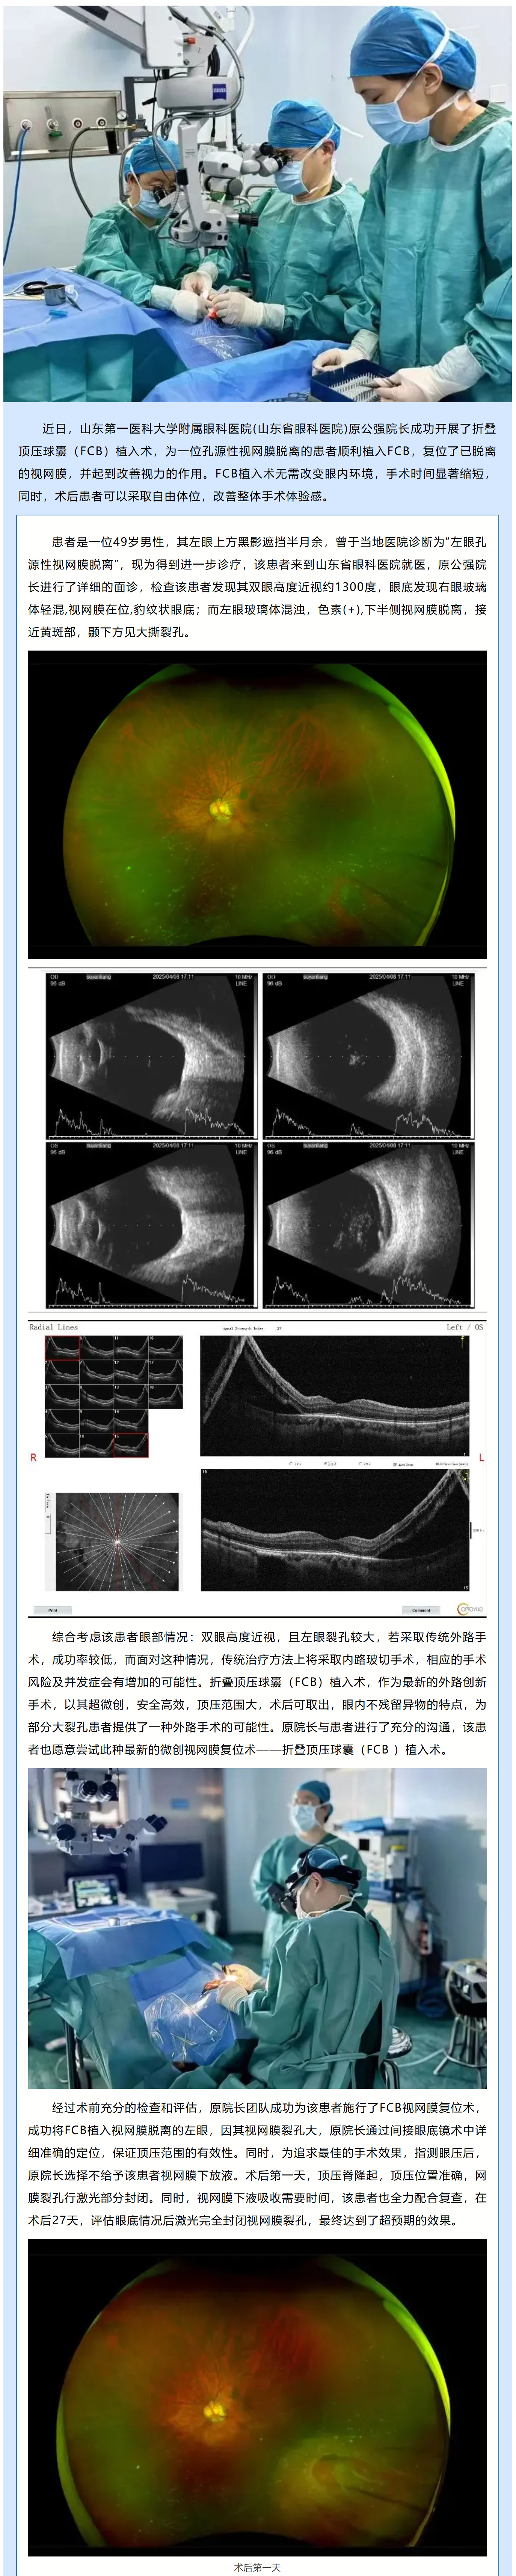

山東第一醫科大學附屬眼科醫院開展FCB手術,為大裂孔視網膜脫離患者提供治療新方式